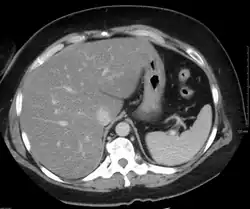

При компьютерной томографии выявляется в разной степени выраженное диффузное снижение денситометрических показателей паренхимы печени (ниже 55 HU, иногда вплоть до отрицательных значений, соответствующих плотности жира), как правило отмечается увеличение размеров органа. Возможно выявление ограниченных участков жировой инфильтрации, окружённых неизменённой тканью печени. Чаще локальная жировая инфильтрация наблюдается в сегменте S4 печени, имеет довольно ровные, прямые контуры, ход сосудов в инфильтрированной жиром ткани не изменён, масс-эффект (объёмное воздействие на окружающие структуры) отсутствует.